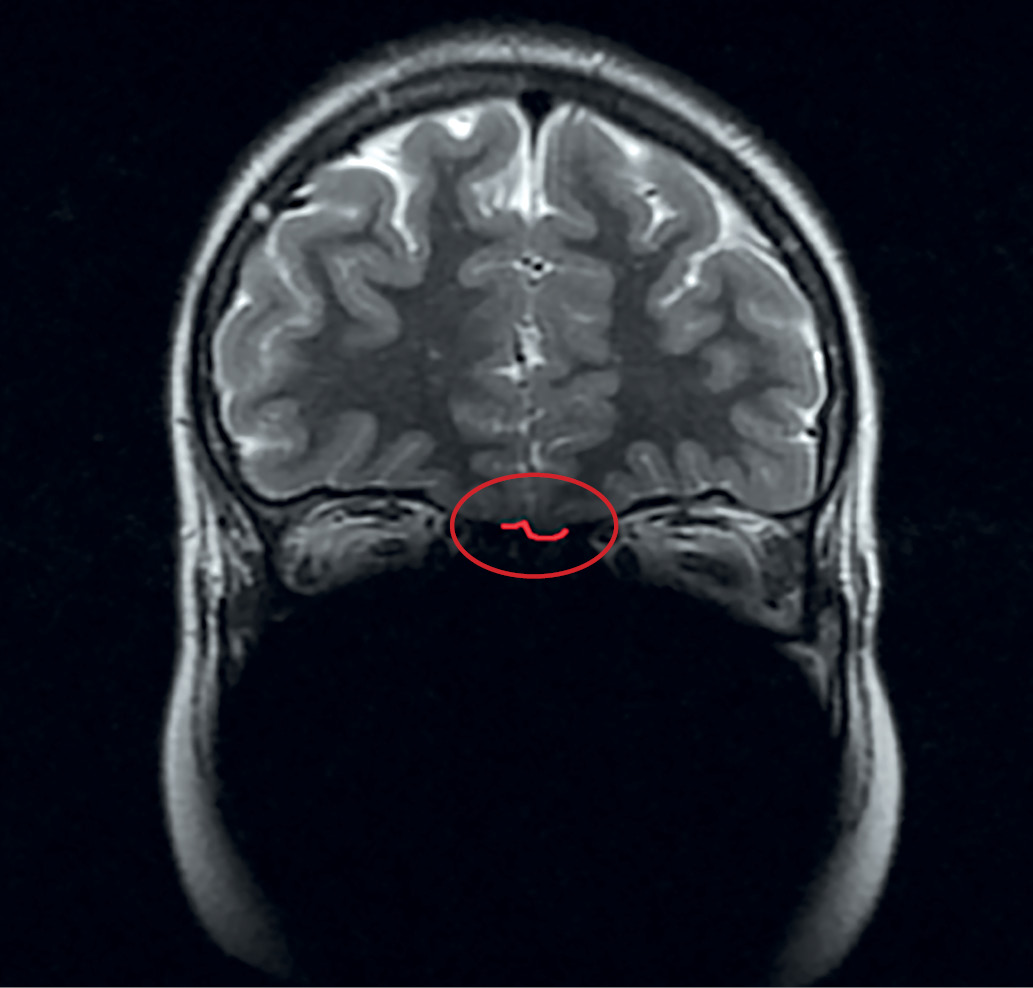

По результатам МРТ у 18 из 19 пациентов с ВИГГ наблюдалось снижение размеров ОЛ или их полное отсутствие. Практически у каждого третьего пациента отмечалась гипоплазия обеих луковиц (7 пациентов). Реже отмечалась односторонняя гипоплазия (27,8%), двусторонняя аплазия (16,6%), гипоплазия одной луковицы в сочетании с аплазией другой (11,1%). Аплазия одной луковицы имелась у 1 пациента. На рисунках 1 и 2 выделена область обонятельных луковиц нормального размера у пациентки из контрольной группы и область с аплазированными ОЛ у пациента с синдромом Кальмана.

Рисунок 1. Нормальные размеры обонятельных луковиц у девочки контрольной группы.